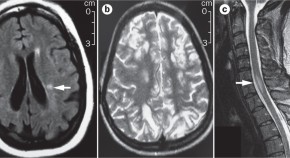

More than 80% of patients with the demyelinating disorder neuromyelitis optica (NMO) experience pain from this condition, which severely affects their quality of life. NMO-associated pain is largely refractory to contemporary pain therapy, suggesting that the mechanisms underlying pain in NMO differ from those underlying other causes of pain. In this article, Bradl and colleagues explore the mechanisms underlying pain in patients with NMO, and attempt to identify molecular and cellular targets for therapy.